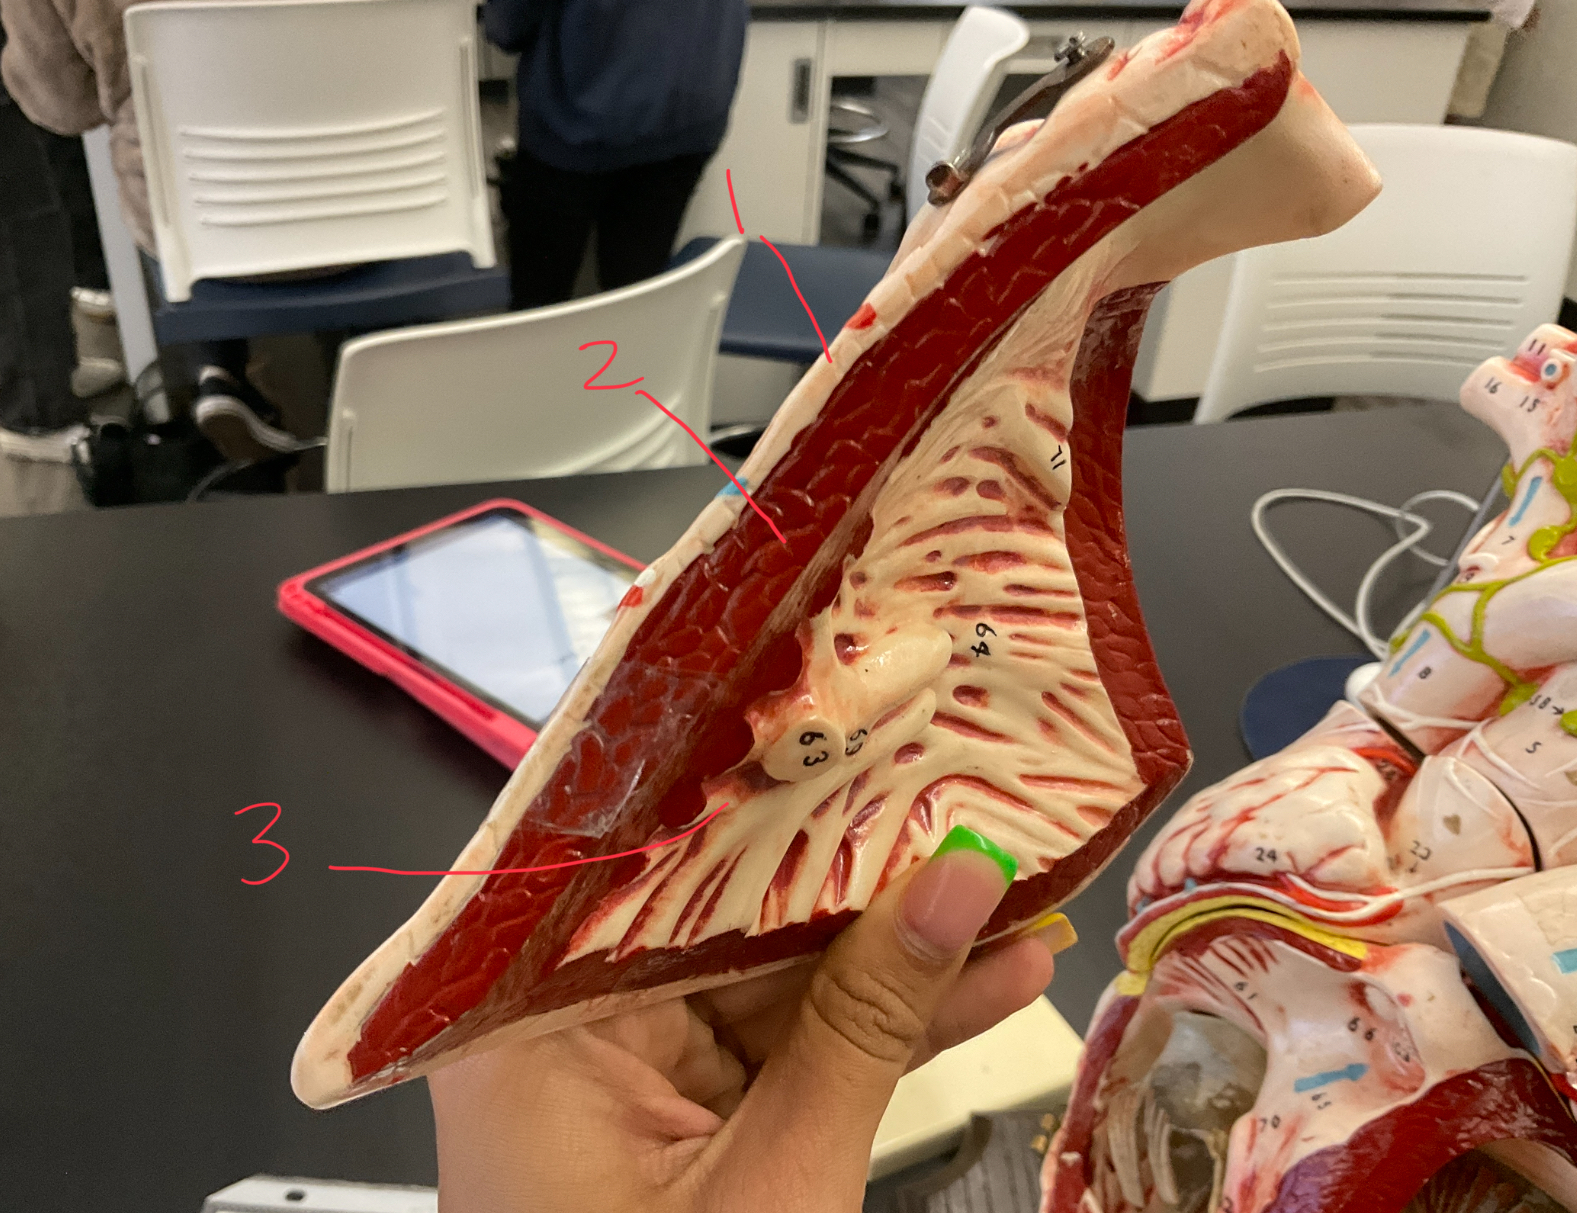

11 (not smooth part)

trubeculae carneae

1

papillary muscle

2

chordae tendineae